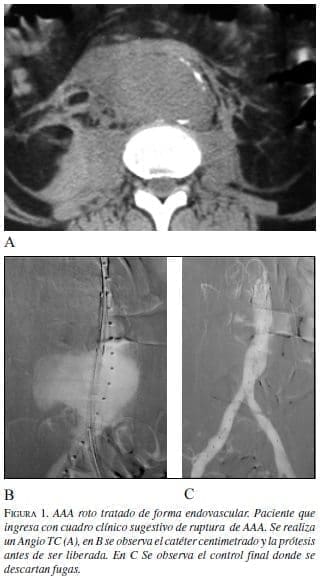

En esta situación se plantea el no hacer nada en caso que el enfermo sobreviva, pero es difícil que los familiares decidan llevárselo del hospital en estas circunstancias. Por lo que debe valorarse la corrección de la rotura (figura 1).

Cuando existen casos de ruptura, las posibilidades de supervivencia ya han sido comentadas con anterioridad. Lo que demuestra que llegando al hospital el índice de mortalidad es menor. Pero si además se aplica cirugía endovascular, las probabilidades de supervivencia de un AAA roto aumentan considerablemente.